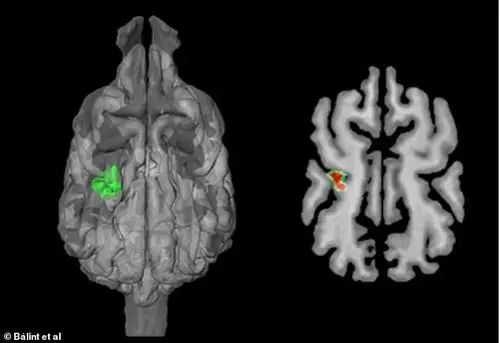

据科学家目前所知,仅有少数动物——黑火甲虫,某些蛇和一种哺乳动物